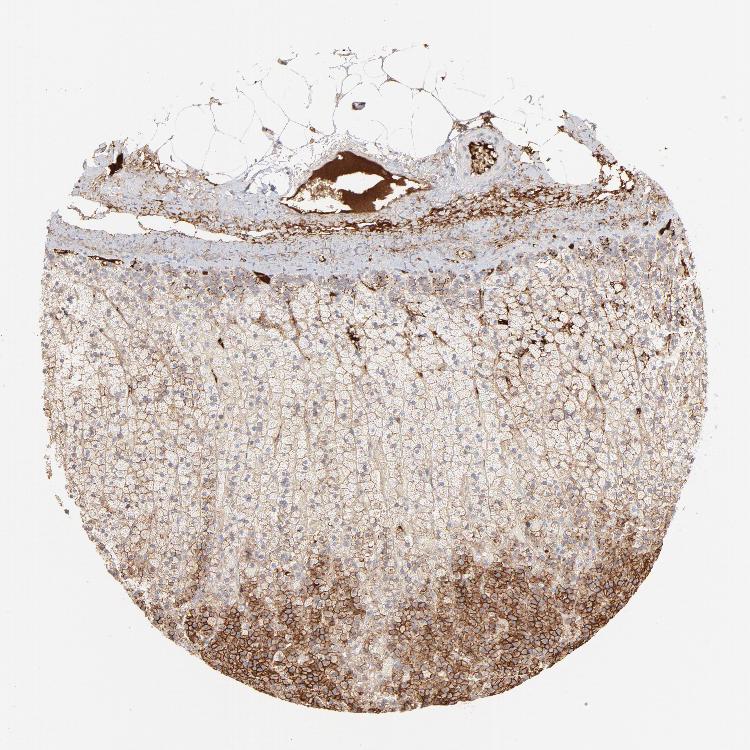

ADRENAL GLAND - Antibody stainingi

Antibody staining in the annotated cell types in the current human tissue is reported as not detected, low, medium, or high, based on conventional immunohistochemistry profiling in selected tissues. This score is based on the combination of the staining intensity and fraction of stained cells.

Each image is clickable and will lead to virtual microscopy that enables deeper exploration of all samples and also displays staining intensity scores, fraction scores and subcellular localization as well as patient and tissue information for each sample.

Antibody CAB003795

Glandular cells High